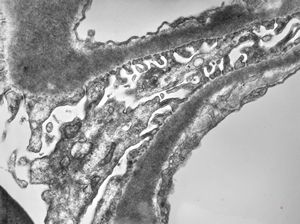

F,14y. | Alport syndrome - split and laminated, thick/thin basement membranes